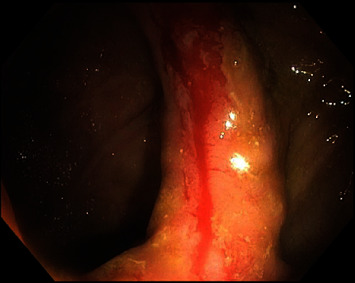

Nonsteroidal anti-inflammatory drugs (NSAIDs) are commonly used to reduce pain and inflammation in over 30 million individuals daily. Gastrointestinal bleeding (GIB) associated with NSAID consumption has been well documented in gastric and duodenal bleeding; however, NSAID-associated GIB distal to the duodenum lacks extensive documentation. This report highlights small bowel occult bleeding related to NSAID use in a patient with a surgical history of robotic total colectomy with ileorectal anastomosis completed 1 year prior. In the case of bright red blood per rectum with associated NSAID use, we recommend NSAID cessation followed by an individualized treatment plan, such as upper/lower endoscopy and/or angioembolization.